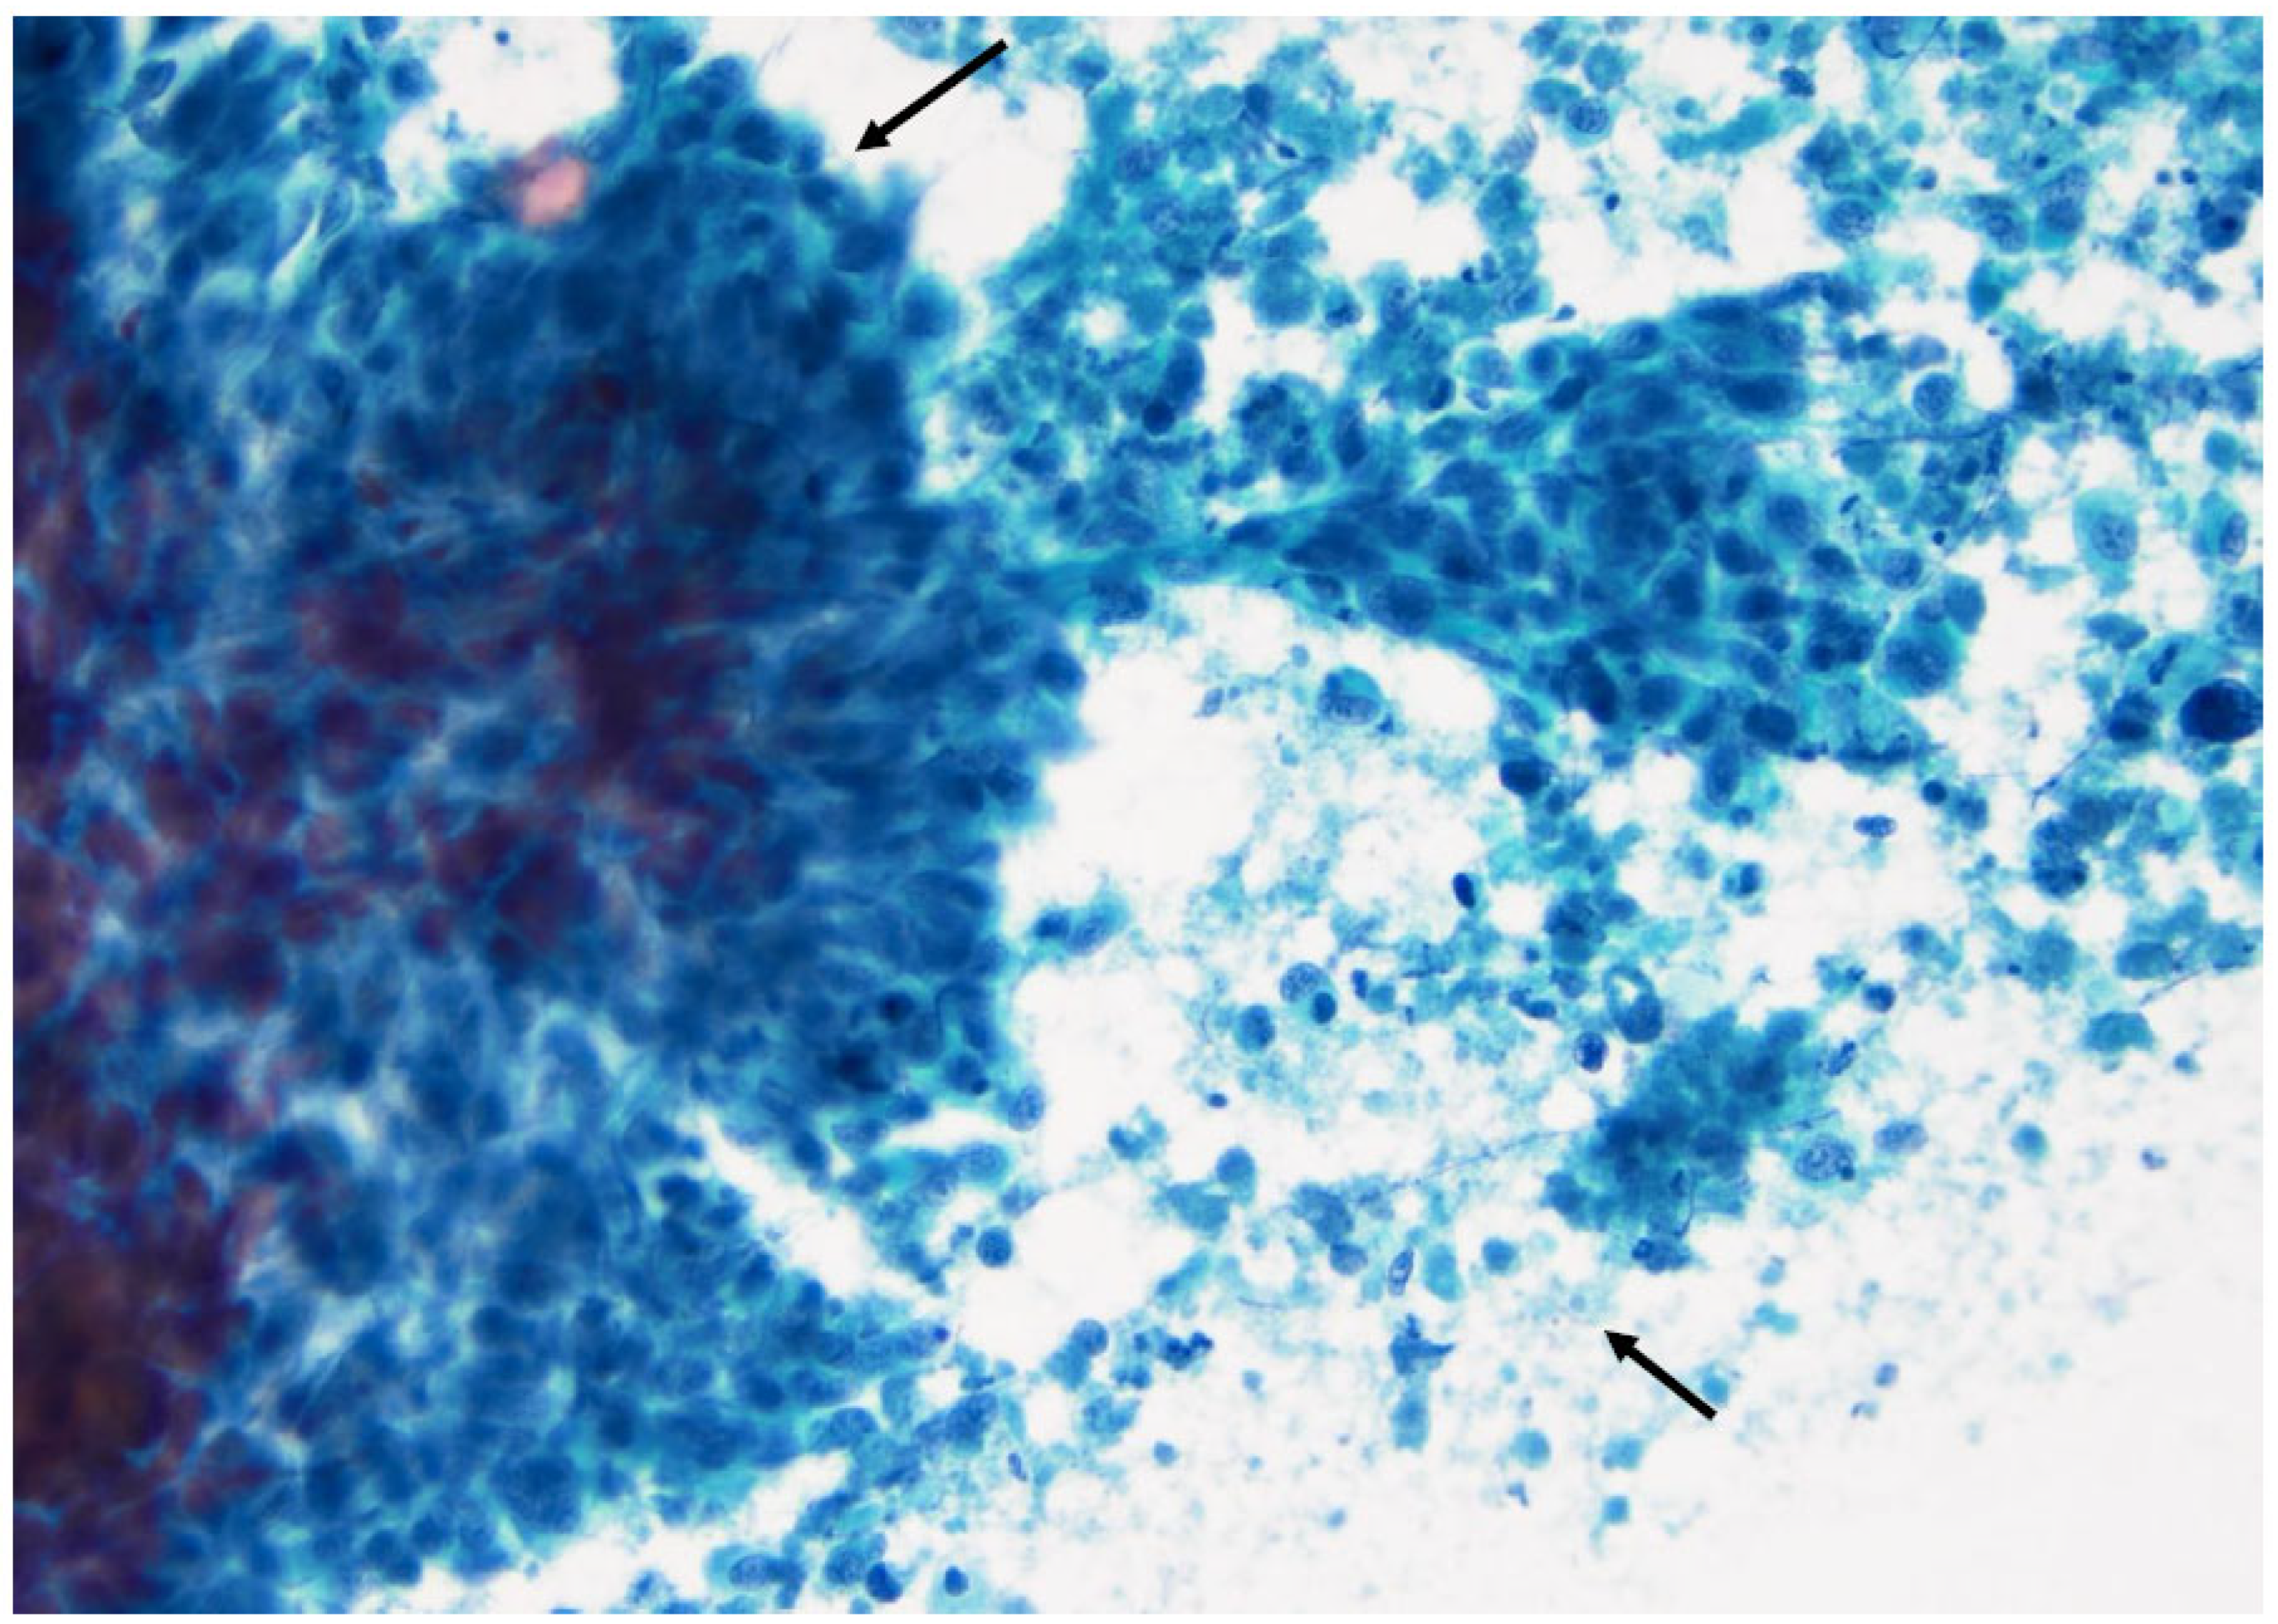

Figure 16. Papillary thyroid carcinoma: note the high cellularity, the large sheets of cells with distinct borders (left arrow), and the naked capillary blood vessel (right arrow) (×200, Papanicolaou stain).